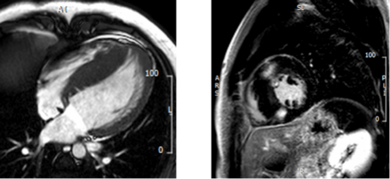

Auf Grund der hohen räumlichen und zeitlichen Auflösung sowie der hervorragenden Gewebedarstellung können mittels kardialer MRT sowohl die Gewebezusammensetzung als auch Funktion aller Herz - und Gefäßanteile exzellent mit hoher Genauigkeit dargestellt und charakterisiert werden. Als nicht-invasives Verfahren, welches ohne ionisierende Strahlung (Röntgenstrahlung) auskommt, ist die kardiale MRT zudem ein äußerst sicheres Verfahren, das auch mehrfache Verlaufsuntersuchungen – beispielsweise bei Herzmuskelerkrankungen – erlaubt. Sie bietet darüber hinaus gegenüber anderen Bildgebungsmodalitäten den Vorteil, das Gewebe des Herzens nicht-invasiv charakterisieren zu können, was sonst nur mittels histologischer Analysen nach Biopsieentnahme möglich wäre. Diese „Gewebecharakterisierung“ erfolgt einerseits mittels spezieller Late Gadolinium Enhancement-Aufnahmen, bei denen die Patient*innen ein gut verträgliches MRT-Kontrastmittel erhalten und andererseits mittels moderner Mapping-Techniken, welche größtenteils ohne Kontrastmittelapplikation auskommen. Durch diese Techniken können Fibrose, Narben (z.B. nach Herzinfarkt) oder Wassereinlagerungen (Ödem) im Herzmuskel festgestellt werden.

Einen großen Stellenwert hat die kardiale MRT in der Ischämiediagnostik bei koronarer Herzerkrankung. Hierbei können mittels pharmakologischer Belastungsuntersuchungen mit Vasodilatatoren (Adenosin) oder mit positiv inotrop wirkenden Substanzen (Dobutamin) Durchblutungs- oder die daraus resultierenden Bewegungsstörungen des Herzmuskels identifiziert werden. Durch diese Methode können mit einer hohen Genauigkeit hämodynamisch relevante Engstellen der Herzkranzgefäße entdeckt sowie deren Auswirkung auf die Herzmuskeldurchblutung bestimmt werden.

Ein weiterer wichtiger Aufgabenbereich der kardialen MRT stellt die Diagnostik und Risikostratifizierungen von primären Herzmuskelerkrankungen (Kardiomyopathien) dar. Neben der Beurteilung der Funktion und Struktur des Herzens ist dabei die Gewebecharakterisierung von herausragender Bedeutung, da insbesondere die Patient*innen, bei denen Vernarbungen und Fibrose im Herzmuskel nachgewiesen werden kann, ein erhöhtes Risiko aufweisen.